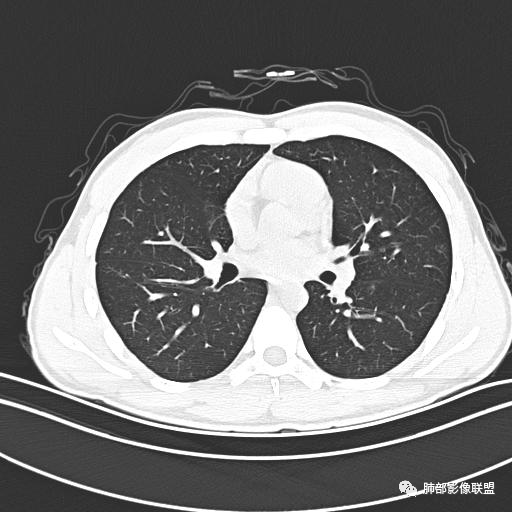

小强:青年,发热,皮疹;双肺散在结节,周围磨玻璃,点晕征,疱疹病毒感染,鉴别荚膜组织胞浆菌,结核。 大雄:青年,急性起病,发热伴全身皮疹2天,抗病毒治疗体温有下降。双肺随机分布大小不等类圆结节,“点晕征”。考虑水痘-疱疹病毒(VZV)血播询问接触史,查体皮疹分布以及形态基本可诊断。 王开金江津中心医院呼吸科:青年男性,起病急,病程短,以发热,皮疹为首发症状,感染指标以单核细胞升高为主,胸部ct双肺多发结界,周围有晕,点晕表现,随机分布,同意於老师意见,水痘疱疹病毒血流感染累及肺。 王秀仙:双肺多发大小不等结节,周围有晕,边缘模糊,呈点晕征表现。青年,急性起病,发热伴全身皮疹2天,抗病毒治疗体温有下降。考虑疱疹病毒。鉴别荚膜组织胞浆菌。 傅昌瑜:19岁男性,发热、全身皮疹2天,单核细胞增高,双肺多发结节,结节边缘见边界不清磨玻璃影。点晕征+发热、全身皮疹+单核细胞增高——考虑水痘-带状疱疹病毒肺炎。 一切∮随缘:年轻男性,发热,皮疹两天,实验室,CRP,PCT增高,影像:双肺多发散在磨玻璃结节,边界欠清,大小不等,呈点晕征改变,以血管束周围分布为主,局部血管束略增粗,其它无明显改变,考虑:1:病毒性肺炎(水痘疱疹病毒?不知道皮肤有无改变)2:真菌(组织胞浆菌,血管侵袭性肺曲霉)3:GPA4:寄生虫(实验室没有看到嗜酸细胞增高) 赵山河:双肺散在结节,周围有晕,边缘模糊,呈点晕征表现。青年,急性起病,发热伴全身皮疹2天,抗病毒治疗体温有下降。考虑水痘—疱疹病毒感染。洪桥爱:青年男性,发热、皮疹2天,伴瘙痒,皮疹于面部首发,之后进展至全身,虽然没有对皮疹进行描述,但是从出疹时间及皮疹进展情况,伴瘙痒,应该就是个水痘患者;CT提示双肺随机分布结节影,部分结节伴有边界不清晕征,考虑水痘血播肺。 刘强:年轻男性,急性起病,皮疹,发热,抗感染治疗体温下降,说明有效。影像表现为散在点晕征,感染类疾病谱(疱疹病毒,真菌,结核),结合年龄,皮肤皮疹,考虑水痘-疱疹病毒性肺炎。 小兜:男性,19岁,发热皮疹两天,颜面部至全身,CRP,降钙素及单核增高。CT示双肺散在小结节,周围伴磨玻璃影,点晕征,考虑为水痘-带状疱疹病毒(varicella-zoster virus,VZV)肺炎 必有路:青年,皮疹+发热+“点晕征”→水痘-疱疹病毒(VZV) 许慧良:青年男性患者,发热、皮疹2天,体温最高38.5℃,第3天皮疹扩展至全身,伴瘙痒,胸部CT:双肺多发随机分布的小结节,结节周边见边界模糊的晕征,考虑水痘病毒感染流心明智:男,19,急性起病,发热伴全身皮疹2天。出疹顺序头→全身,抗病毒有效。胸部CT:两肺多发大小不等类圆形实性小结节影,随机分布,结节周围环绕GGO,边界模糊,呈点晕征。出疹特点是关键,未提示。考虑:血播病毒性肺炎,水痘-疱疹病毒?麻疹?鉴别荚膜组织胞浆菌、TB、血管炎、寄生虫等。 浪迹天涯:病灶多为5-10mm大小结节,结节周围可见磨玻璃样的晕环,常多发,可分布于肺内任何区域,考虑水痘—带状疱疹病肺炎如果短时间内有新的一个区域浸润,更加能说明,